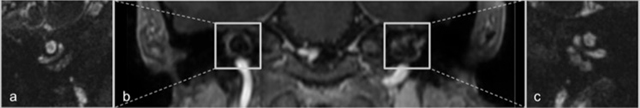

Figure 2

Coronal reconstructions of contrast-enhanced 3D FFE-imaging demonstrates symmetric areas of contrast enhancement in the pericochlear regions (b) Hyperintense signal anomalies are seen around the basal turn of the cochlea in the right (a) and left temporal bones (c) on 3D balanced steady-state gradient echo-imaging.